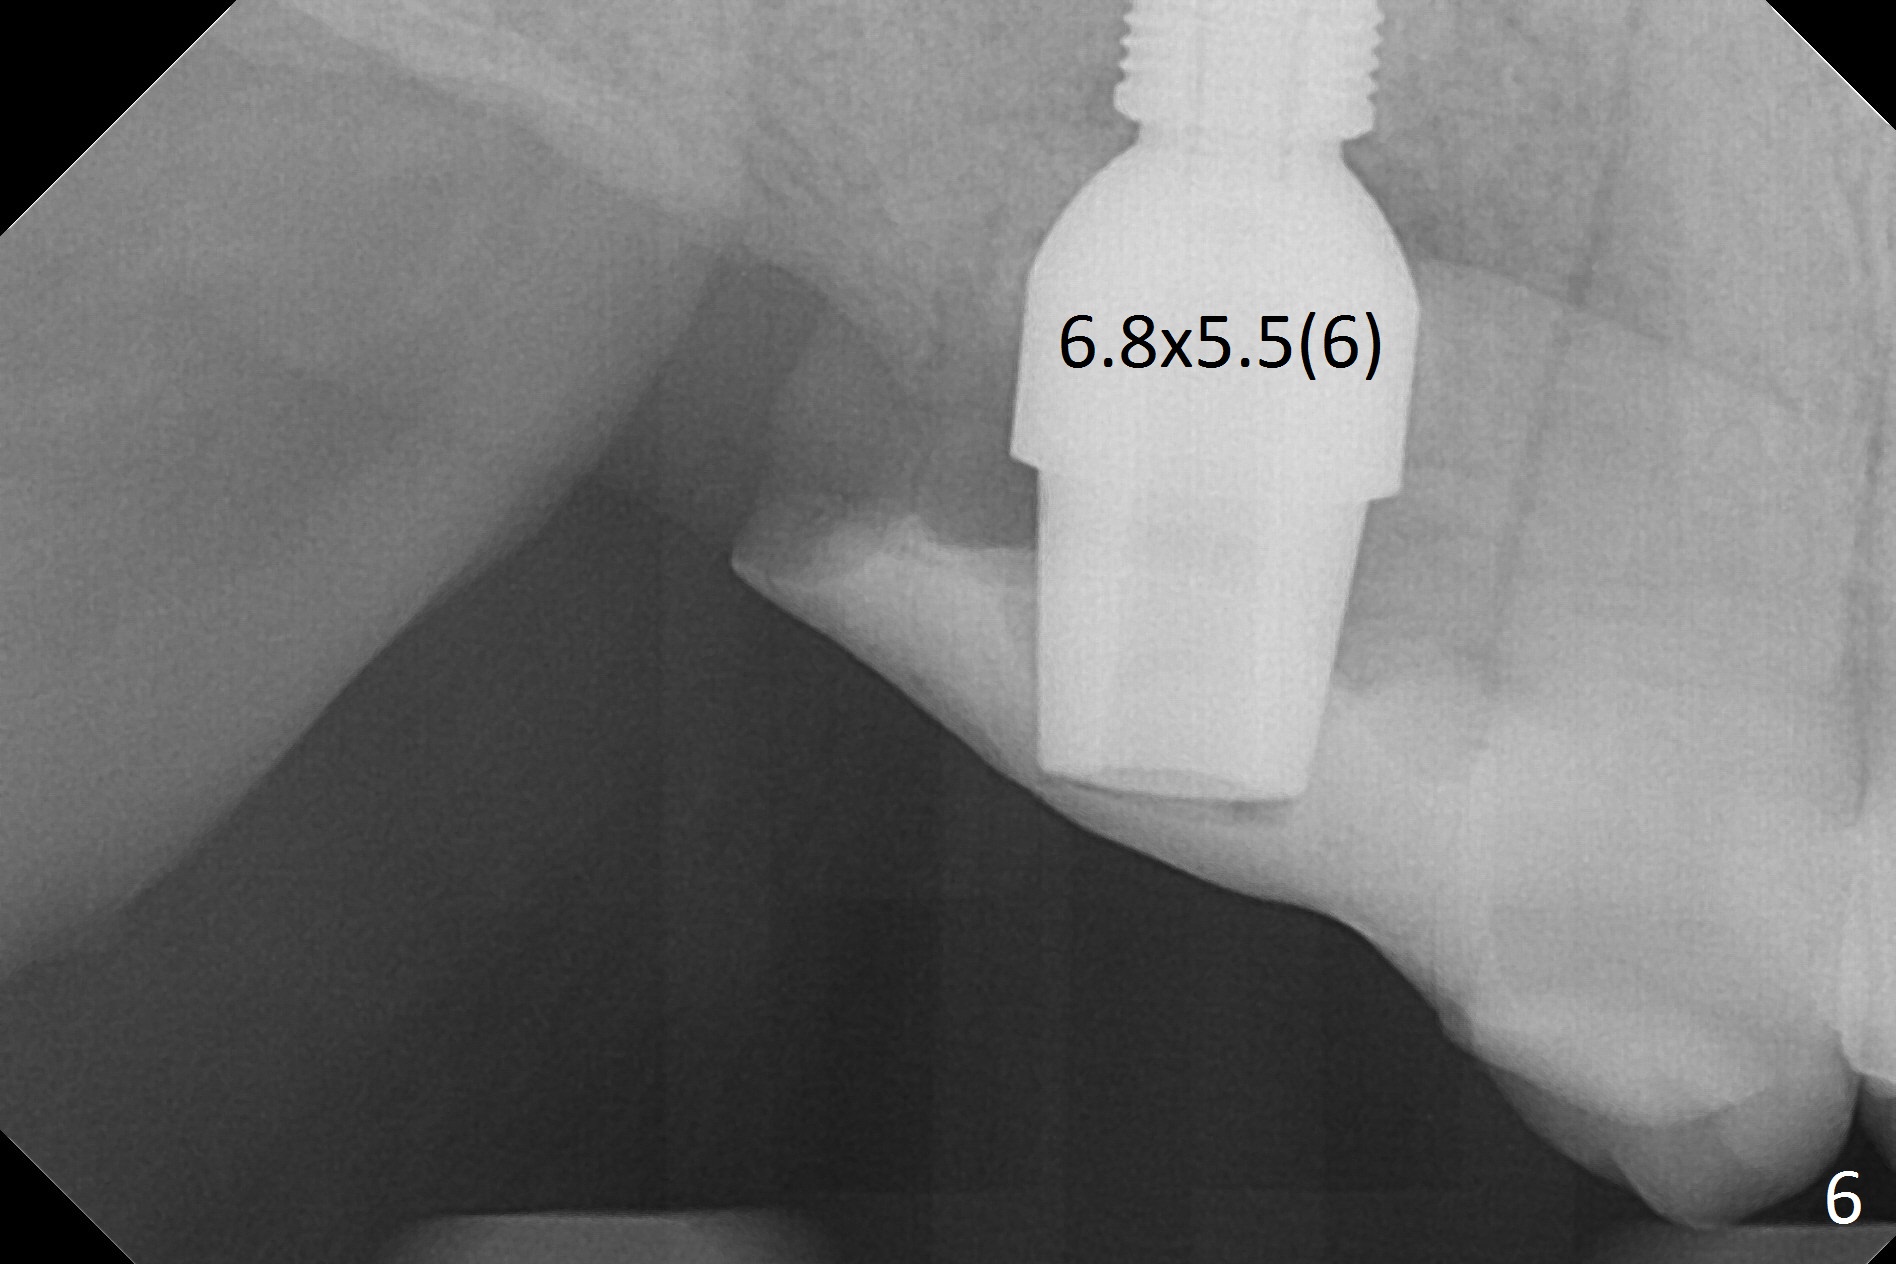

The palatal socket (Fig.1 P, packed with gauze) is intact, but implant trajectory may not be ideal. Buccal to the palatal socket are 2 pieces of the gingiva, buccal (B) and Septal (S). After the septal gingiva is pushed buccally (Fig.2 arrow), the underlying sloped septal bone is exposed (Fig.3 white area). Osteotomy is established as palatal as possible (Fig3 black circle) using DIO Sinus Master Kit, supplemented by Tatum osteotomes and DIO SM 3.8 mm tap drill for final sinus lift (Fig.4). Following further osteotomy using 4.1 and 4.5 mm taps, a 4.5x10 mm implant (Fig.6,7) with insertion torque >65 Ncm. Due to buccal bone loss, the coronal buccal threads are exposed 1-2 mm, which is covered by combination of allograft, autogenous bone and Osteogen. Prior to implantation, PRF plug and bone graft are used for sinus lift. The septal gingiva now is approximately 1-2 mm coronal to the implant plateau (Fig.5 S). The most coronal buccal gingival defect is covered by 3 pieces of PRF membrane (Fig.5 M) against a 6.8x5.5(6) mm abutment (A). Finally the socket is protected by periodontal dressing (Fig.8).